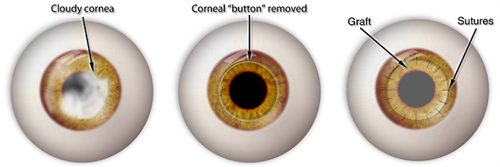

穿透性角膜移植:4.5万元起/单眼

适用人群:全层混浊或穿孔(如化学伤、溃疡)

含金量:飞秒激光辅助切口(精度0.1mm),术后散光降低40%

注:以上费用含术前检查+手术费+3天住院,供体角膜免费(源自无偿捐献)。

飞秒激光移植系统实现微米级切割,供体利用率提升40%

排斥率控制在<10%(低于医院的15%)